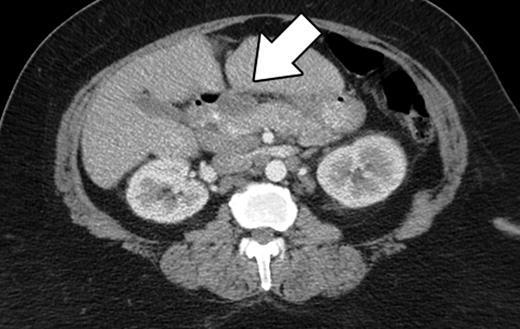

The patient is an asymptomatic 60-year-old African American female, who was referred to our institution for an elevated CA19-9. Her past medical history included diabetes mellitus, asthma, hypertension, hypercholesterolemia, obstructive sleep apnea and osteoarthritis. She denied abdominal pain, decreased appetite, nausea, vomiting, diarrhea, pruritus, jaundice, acholic stool or dark urine. She had no fevers, night sweats or other constitutional symptoms. She denied alcohol or tobacco use. Her family history was significant for colon and breast carcinoma. Her vital signs were within normal limits. She had no lymphadenopathy on examination of the head and neck. Abdominal exam revealed an obese, soft, non-tender, non-distended abdomen with no hepatosplenomegaly. The cardiovascular, neurologic and pulmonary exams were unremarkable. Computer tomography (CT) scan of her abdomen revealed a smooth shaped lesion involving the pancreatic head, measuring 3.6 cm at its greatest diameter (Fig. 1). Mesenteric lymphadenopathy was also noted, with the largest node measuring 2.3 cm in diameter. The liver, spleen, gallbladder and cystic duct were normal. These CT findings were consistent with pancreatic neoplasm and prompted surgical referral. After consultation, the patient agreed to a Whipple procedure. An endoscopic ultrasound (EUS) or fine needle aspiration biopsy was not preformed preoperatively.